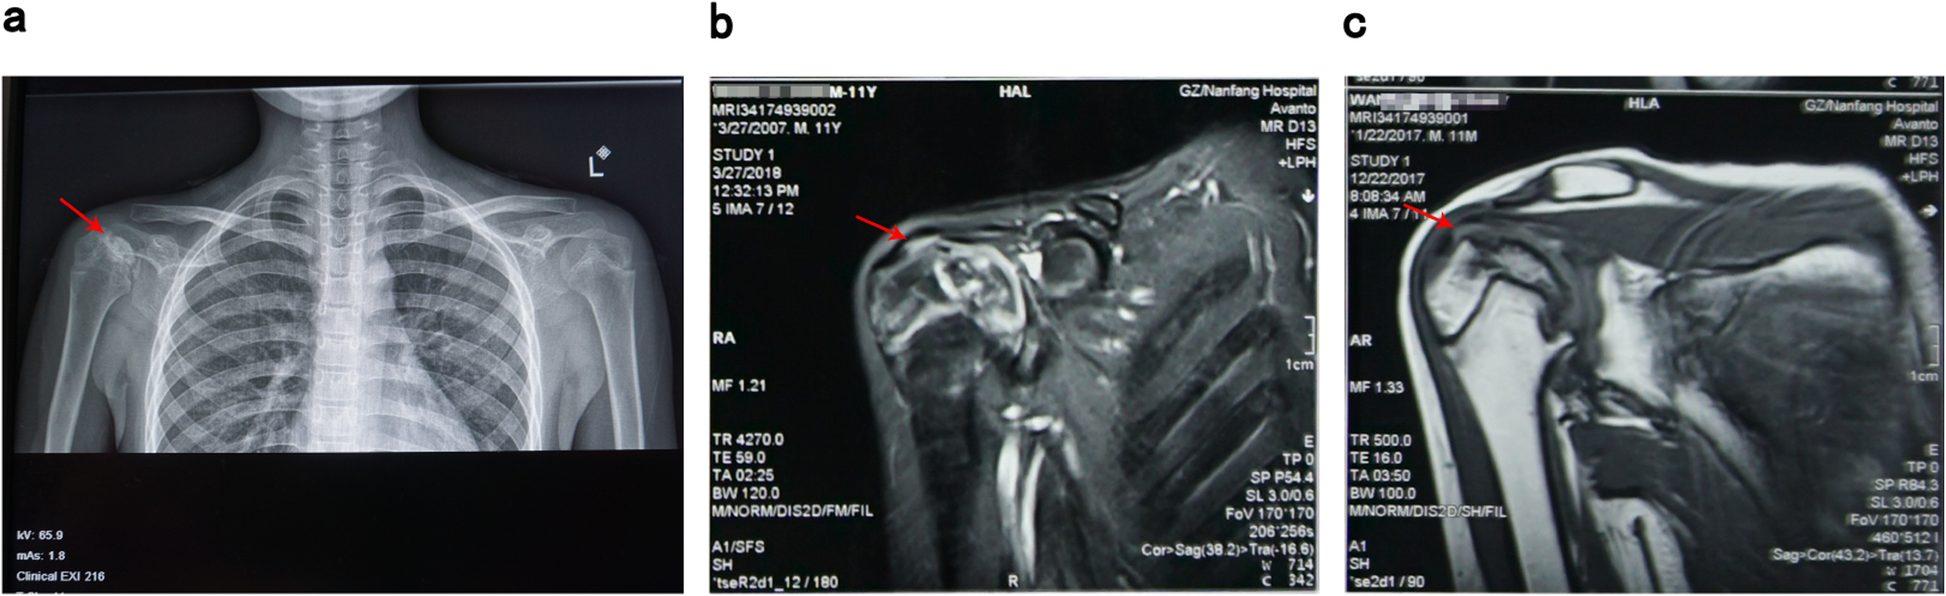

Fig. 3

X-ray imaging (a) and magnetic resonance imaging (b, c) results of right shoulder joint (The arrows point out pathological structures in examinations, indicating necrosis of the right shoulder osteoepiphysis)